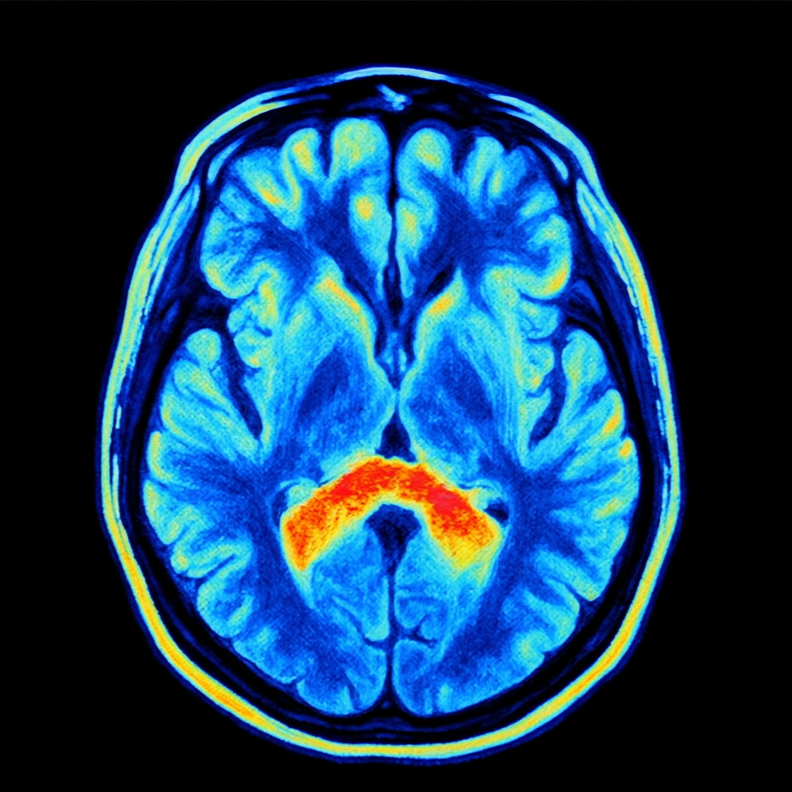

Predicting the Existence of Dyslexia in Children Using fMRI